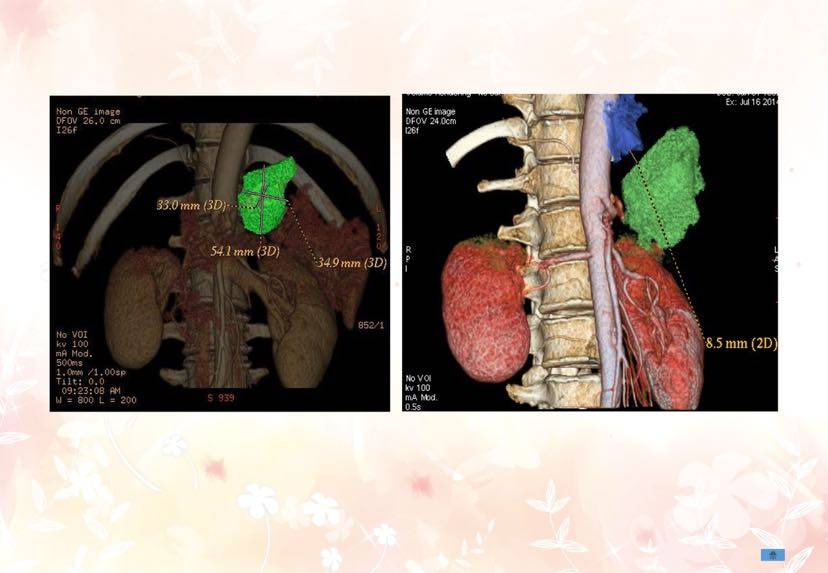

第二步:用放射性碘125粒子,通过三维立体成像技术(3D影像),铺助3D建模精准植入到肿瘤内部,在内部持续杀死肿瘤,不伤害正常细胞。